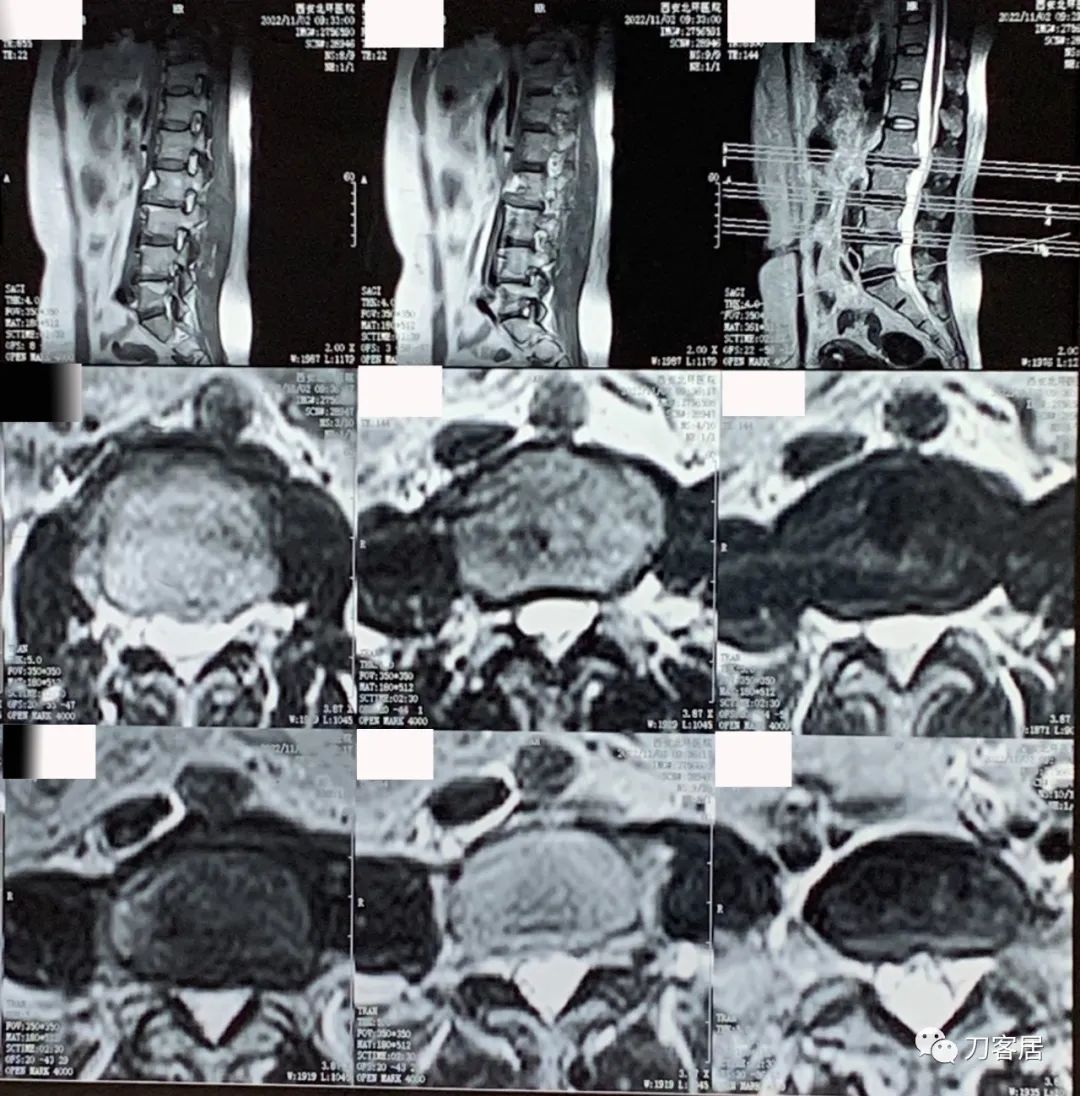

图4. 20221102西安北环医院腰椎MRI04